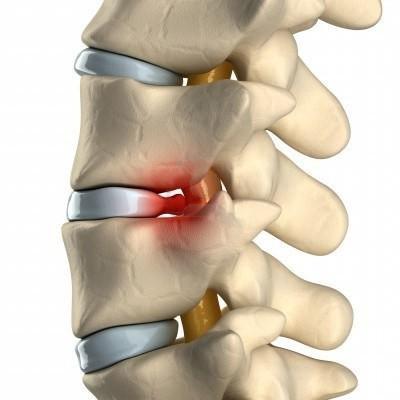

- Остеохондроз – процесс разрушения межпозвоночного диска, при котором позвонки сближаются, защемляя нервы. Обостряется сезонно, после гиподинамии, нагрузок. Боли длительные, средней интенсивности, разлитые. Схожая симптоматика, обычно, наблюдается и в суставах других групп;

- Грыжа, протрузия межпозвоночного диска – выход диска или его содержимого за пределы позвоночного столба, в спинномозговой канал. Происходит сдавливание большого количества нервной ткани, потому кроме очень интенсивных болей наблюдаются онемения ног, гипертонус, спазм мышц в них, их слабость;

Межпозвоночная грыжа

Поясничные грыжи обычно находятся между третьим, четвертым и пятым поясничными позвонками и между пятым позвонком и крестцом. Зачастую грыжей защемляются нервы, ведущие в нижние конечности. Боль при межпозвонковых грыжах острая. Больному тяжело нагибаться, вставать, порой даже лежать на ровной поверхности.